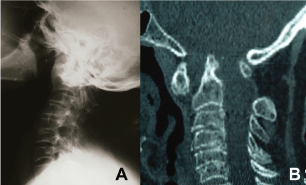

Some algorithms were created to guide the therapeutic planning of these patients [32]; However, the emergence of new knowledge about the pathophysiology of the disease and the development of new surgical techniques such as those described above allowed different strategies, resulting in more benefits and less morbidity for the patients. Thus, we are proposing a new therapeutic algorithm, as illustrated in Figure 6.

Figure 6: Therapeutic algorithm to RA of CVJ. View Figure 6